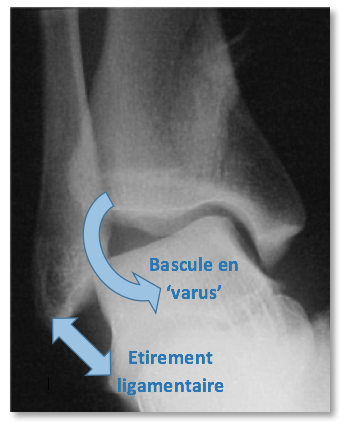

L’entorse typique de cheville se produit lorsque l’astragale (et tout le pied avec) bascule sous le bloc tibia-péroné, pied en dedans (Images 3 et 4). C’est un mécanisme dit en ‘varus‘. Les faisceaux du ligament latéral externe sont alors +/- étirés. Au premier stade, il s’agit simplement d’une entorse bénigne, incomplète, du faisceau antérieur. Le stade le plus évolué est l’entorse grave (c’est-à-dire avec rupture complète) du faisceau antérieur et du faisceau moyen. Tous les stades intermédiaires sont possibles Le faisceau postérieur n’est généralement pas atteint.

Image 3 : Mécanisme de l’entorse du ligament externe sur une radiographie de face